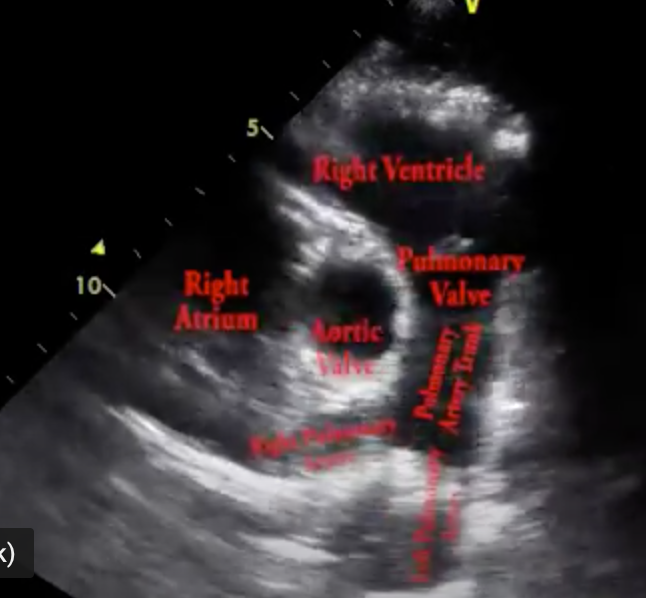

Q

In this PLAX view, the arrow is pointing to the:

A

RCC

The arrow (gray one) in this image is pointing to the:

Left main coronary artery

*the image demonstrates the left coronary artery originating from the left coronary cusp